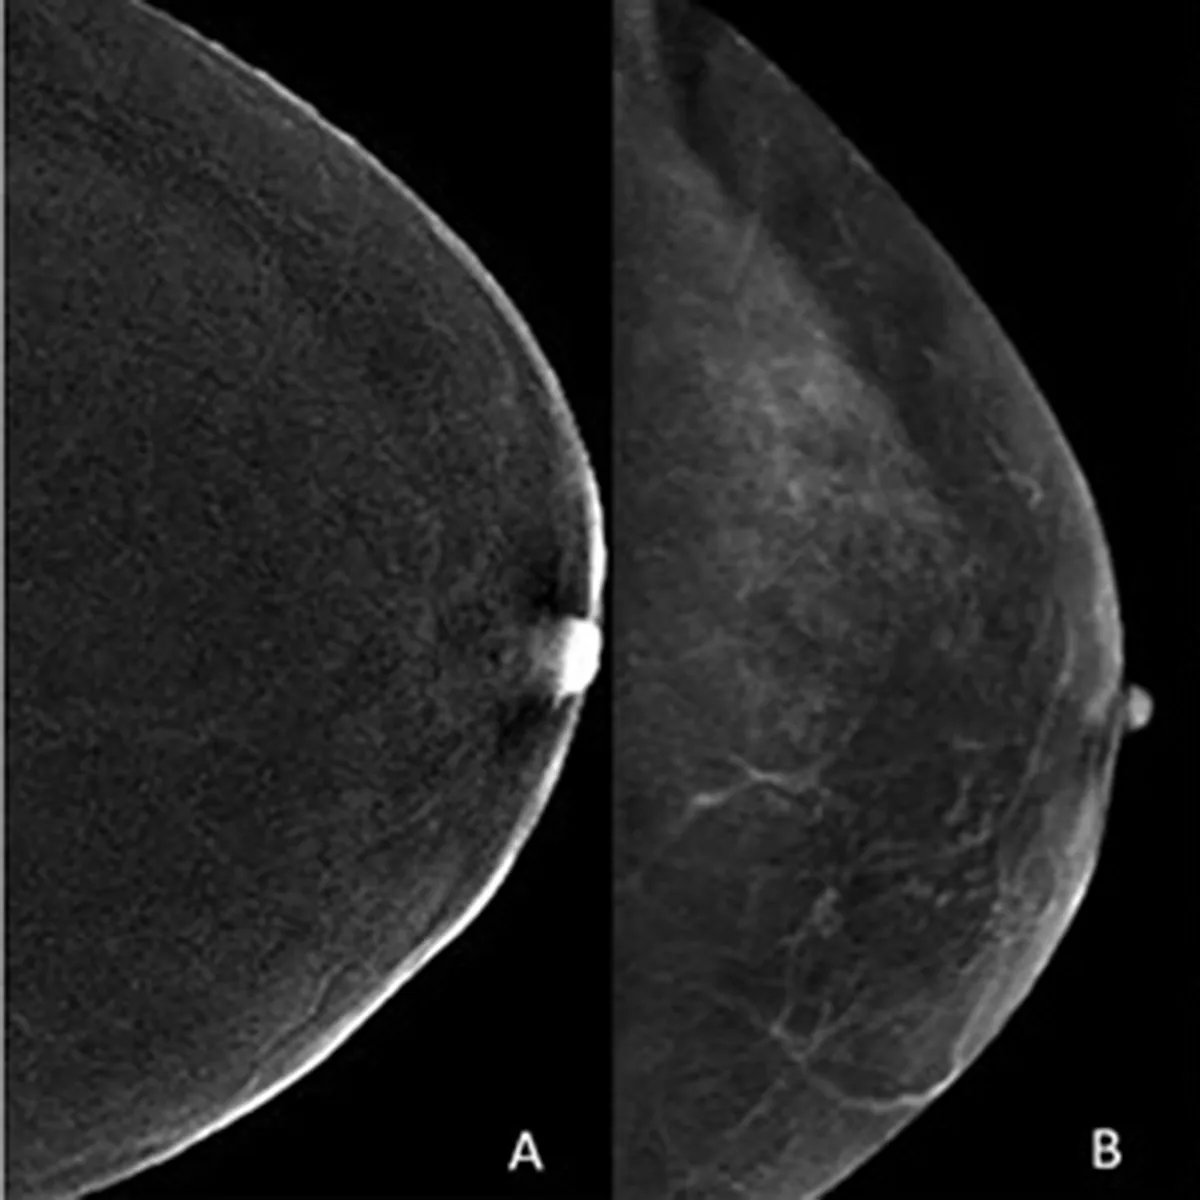

New @AJR_Radiology Accepted Manuscript: "Challenging Contrast-Enhanced Mammography-Guided Biopsies: Practical Approach Using Real-Time Multimodality Imaging and a Proposed Procedural Algorithm" By Drs @OWeaverMD & team @MDAndersonNews ajronline.org/doi/abs/10.221…

Sharing our interim excellent results on screening contrast-enhanced mammography in women with a personal history of breast cancer, presented #RSNA2022. Thank you @BCRFcure @LaneBryant for your support! @PittRadiology medicalresearch.com/contrast-enhan…